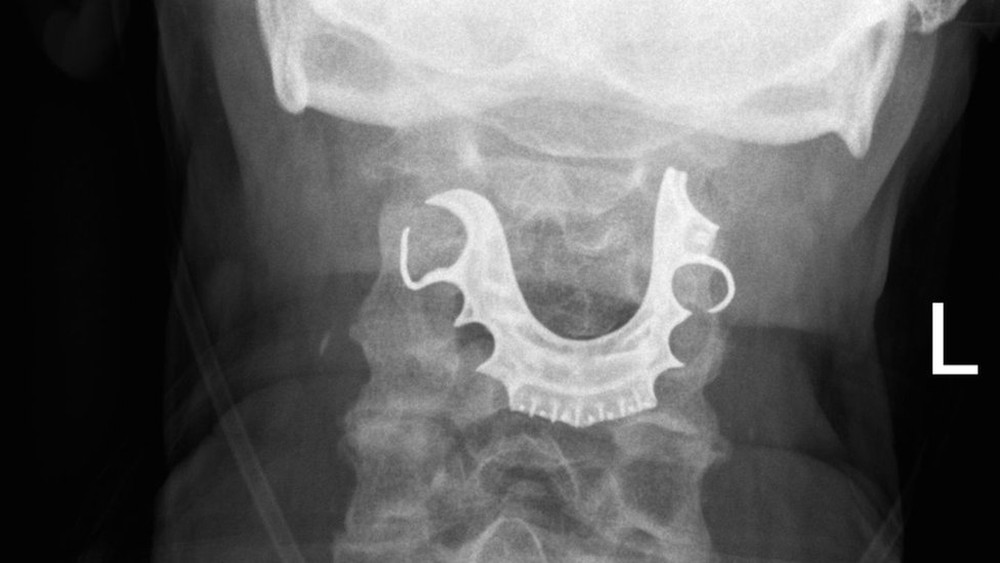

Quando o homem voltou, dois dias depois, a equipe médica examinou mais detalhadamente e encontrou um objeto semi-circular sobre as cordas vocais.

Ele então disse aos médicos que havia perdido sua dentadura - três dentes falsos e uma placa dentária - durante o tempo em que ficou no hospital para a cirurgia.